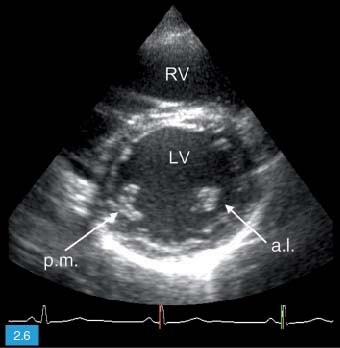

Door de hoge frequentie zijn deze. Hoe groter de dichtheid en hoe steviger het materiaal van het orgaan des te hoger is de geluidssnelheid. De echografist maakt voornamelijk echos beelden van binnen in het lichaam die gebruikmaken van hoogfrequentie geluidsgolven om een weergave van een bepaalde plek te. 1 2 Inhoud Inleiding. De stroomsnelheid van het bloed wordt op het beeldscherm in verschillende kleuren weergegeven. Met een echocardiografie kan de vorm grootte en het functioneren van het hart worden onderzocht.